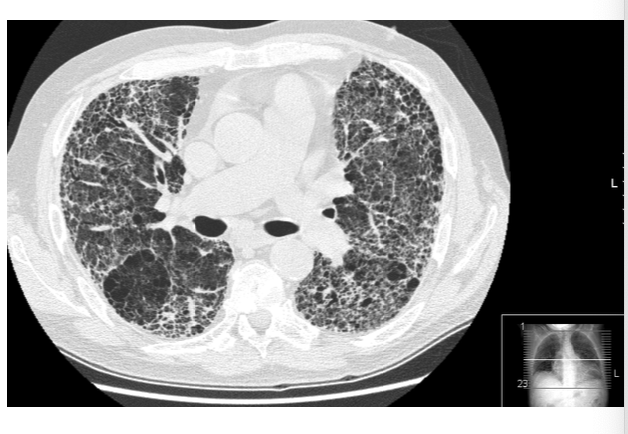

what is depicted in the image?

CT scan showing idiopathic pulmonary fibrosis, notice the diffuse interstitial pattern, the tissue vs open space, and the ground glass opacity